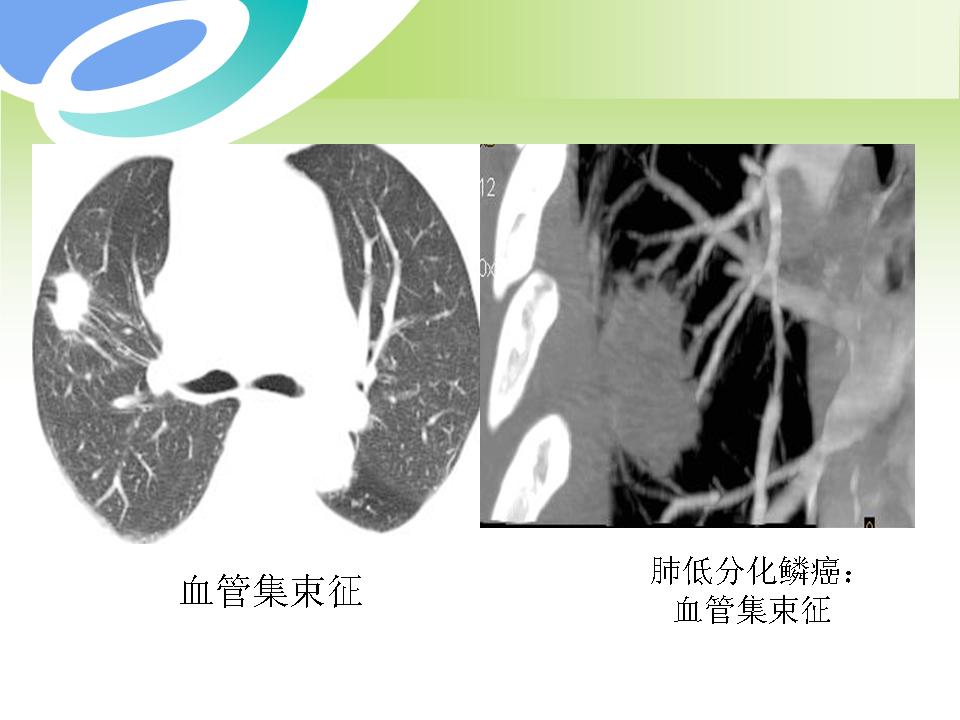

肺部病变的CT基本征象